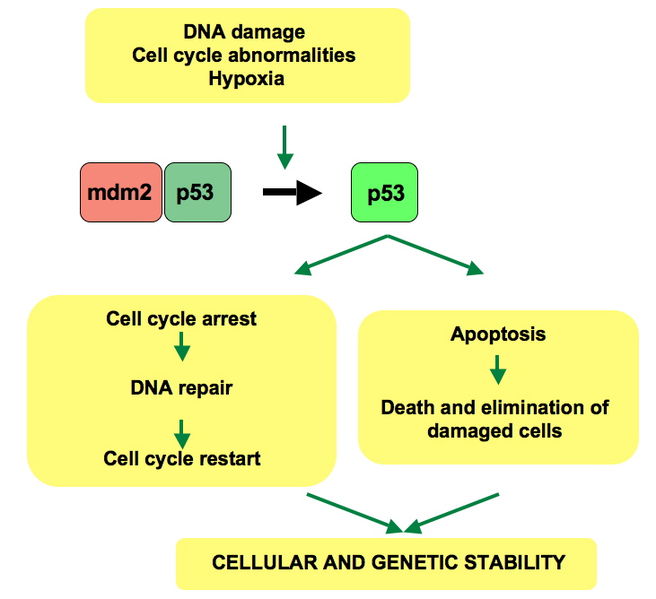

TSS: transcriptional start site;

TTS: transcriptional termination site